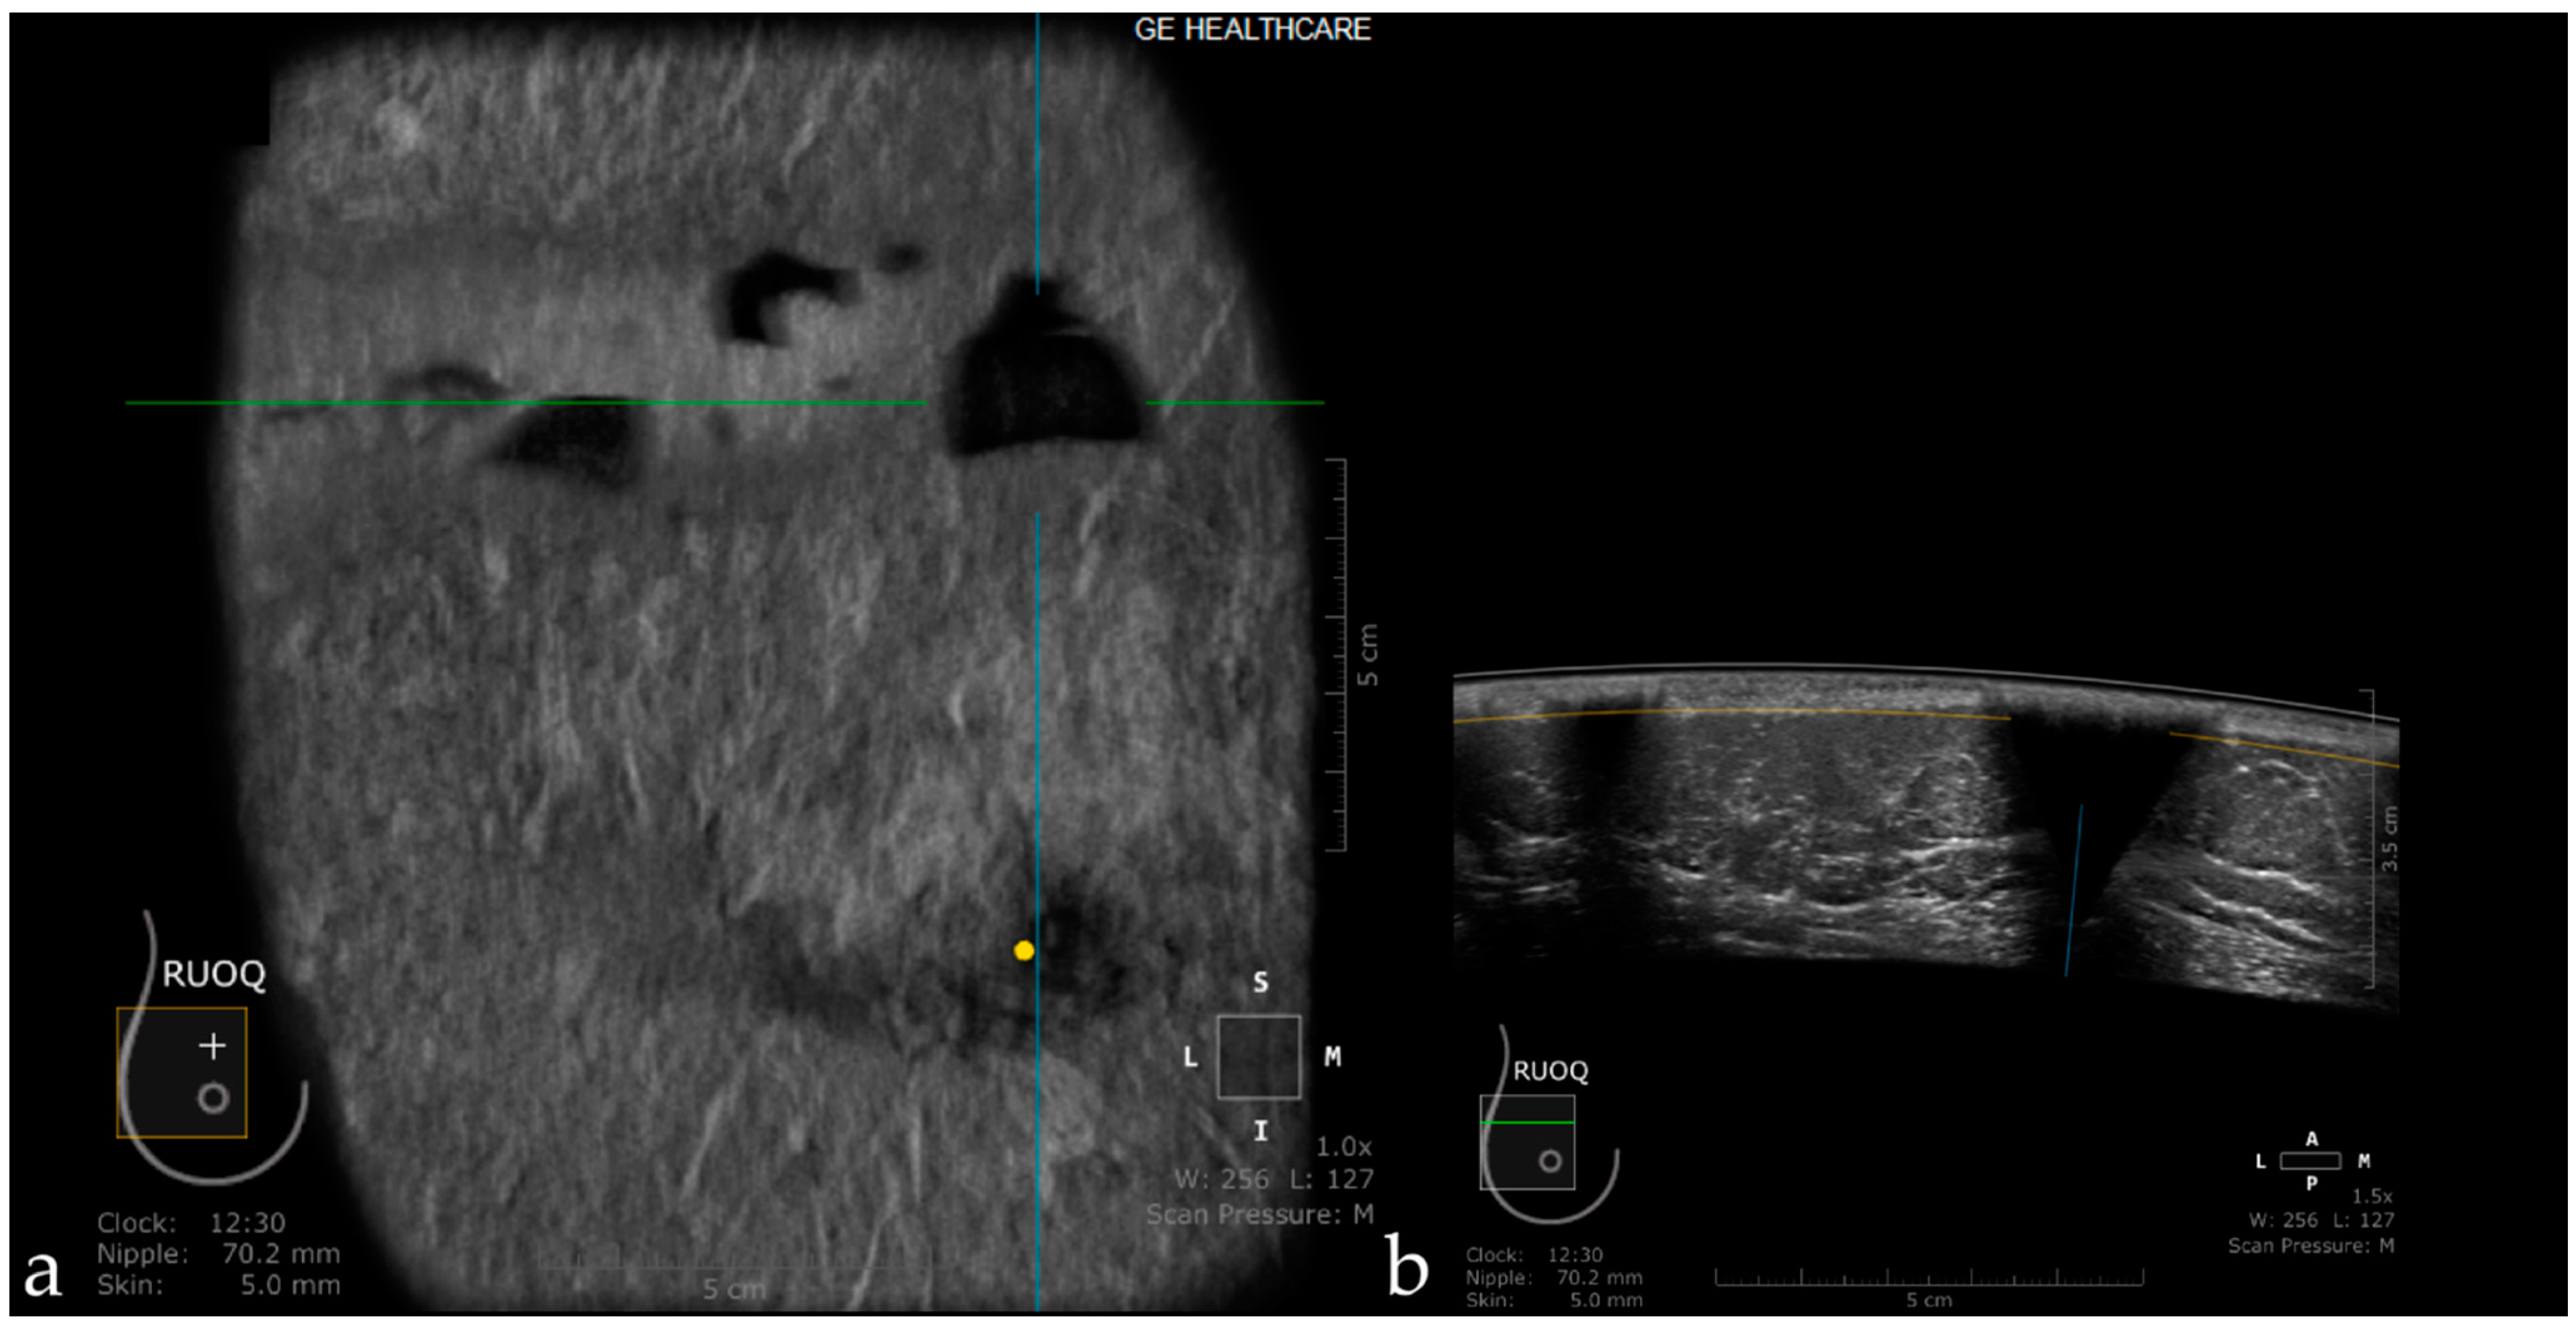

Artifacts Induced by the Use of Ultrasound Gel

- Karst, I.; Henley, C.; Gottschalk, N.; Floyd, S.; Mendelson, E.B. Three-dimensional automated breast us: Facts and artifacts. Radiographics 2019, 39, 913–931. [Google Scholar] [CrossRef]